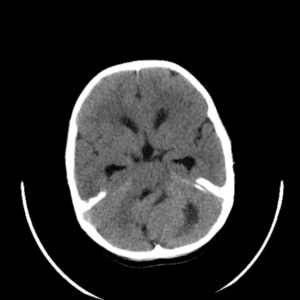

Case #2

Cavernous malformation